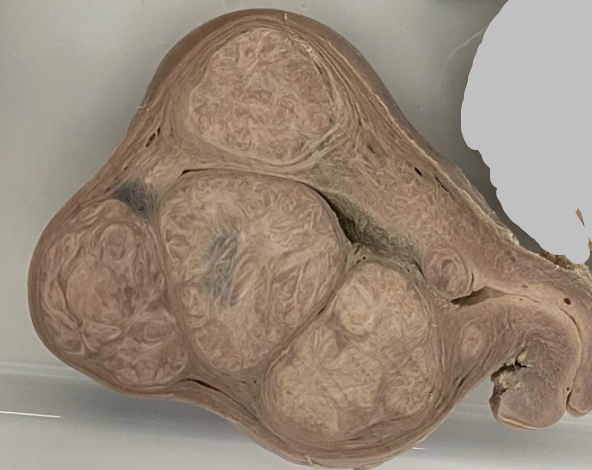

-Órgão: Útero.

-Descrição: Útero aumentado de tamanho, com presença de tumor benigno, bem delimitado com

características semelhante ao do tecido normal.

-Diagnóstico: Leiomioma submucoso, intramural e subseroso.